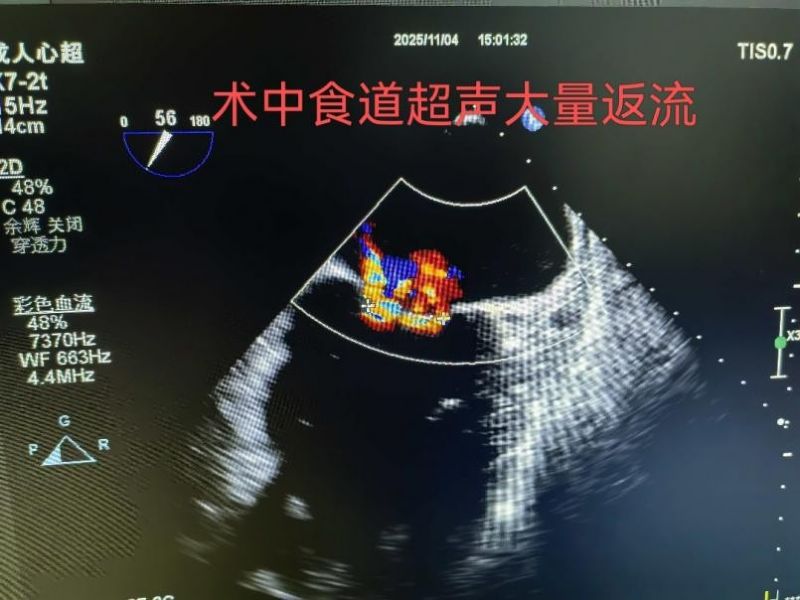

手術(shù)于11月4日下午進(jìn)行,通過(guò)股靜脈穿刺送入夾合器,在食道超聲實(shí)時(shí)引導(dǎo)下,精準(zhǔn)植入2枚瓣膜夾修復(fù)二尖瓣。整個(gè)過(guò)程歷時(shí)約2小時(shí),術(shù)中出血量?jī)H50ml。術(shù)后次日,患者即可下床活動(dòng),復(fù)查顯示EF提升至46%,二尖瓣返流面積縮小至3.0cm2,左心房縮小至66mm,胸悶、氣短癥狀明顯緩解。

2.精準(zhǔn)定位:在食道超聲和X線引導(dǎo)下,將夾合器送達(dá)二尖瓣位置,通過(guò)夾合病變瓣膜減少返流;